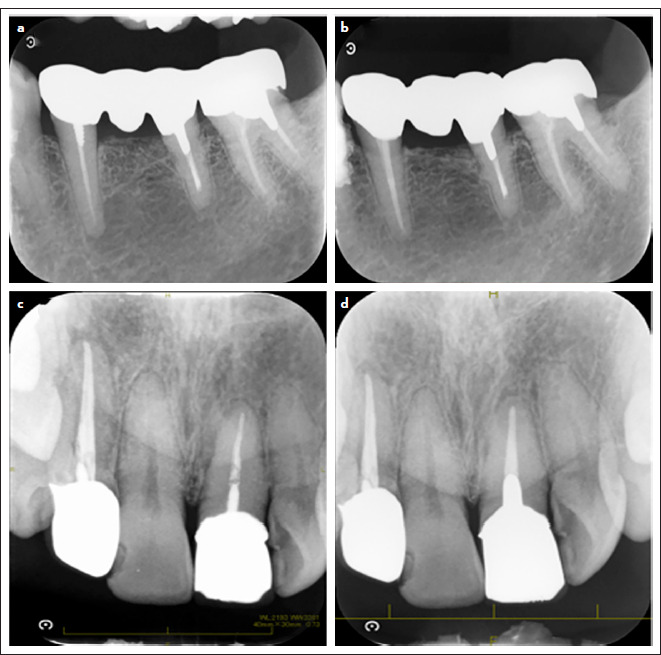

Objective: To investigate the effect of increasing the apical size of roots enlarged for root canal obturation on the outcome of non-surgical endodontic treatment for teeth with apical periodontitis.

Methods: In this retrospective study, we included 210 cases of single-rooted canals treated at our dental units between October 2009 and January 2022. The clinical outcomes of teeth with enlarged root apical size from the International Organization for Standardization standard numbers 25 to 100 were investigated.

Results: The number of teeth with a root apical size of ≤50 and ≥ 55 were 158 and 52, respectively. In the former case, 144 (68.6%) teeth had good prognoses and 14 (6.7%) had poor prognoses. In the latter case, 28 (13.3%) teeth had good prognoses and 24 (11.4%) had poor prognoses.

Conclusion: Unfavourable clinical outcomes were observed in root canal-filled teeth with an enlarged apical root size of ≥ 55. Thus, these sizes potentially indicate poor outcomes of nonsurgical endodontic treatments.